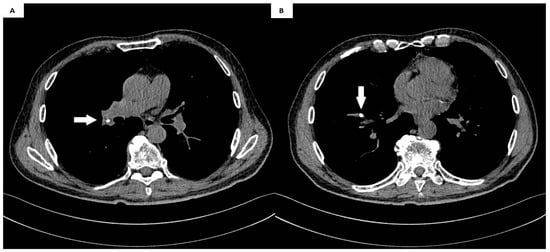

| Presented case | M | 67 | Gastric cancer | Cough, weakness, nausea, and heartburn | Right pulmonary artery | 8 | Thoracotomy |